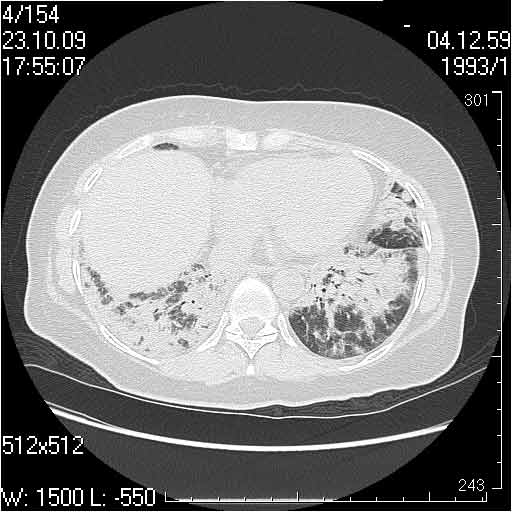

Случай №3

Женщина 51 год

Случай 3:смешанные изменения; подходят для интерстициальной пневмонии, тактика аналогична случаю 1.